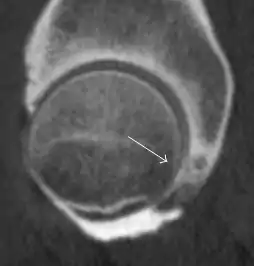

Figure 7:

- Axial CT image of pigmented villonodular synovitis eroding the posterior cortex of the femoral neck.[1]

- Sagittal T2* gradient echo image showing a posterior soft tissue mass with hypointense areas secondary to hemosiderin deposition.[1]

In synovial proliferative disorders, MRI demonstrates synovial hypertrophy. In the case of PVNS, characteristic foci of low signal intensity related to hemosiderin deposition are better seen on gradient echo T2* images (Figure 7). In the case of synovial osteochondromatosis, the synovial hypertrophy is accompanied by intermediate signal cartilaginous loose bodies and/or low signal calcified loose bodies.[1]